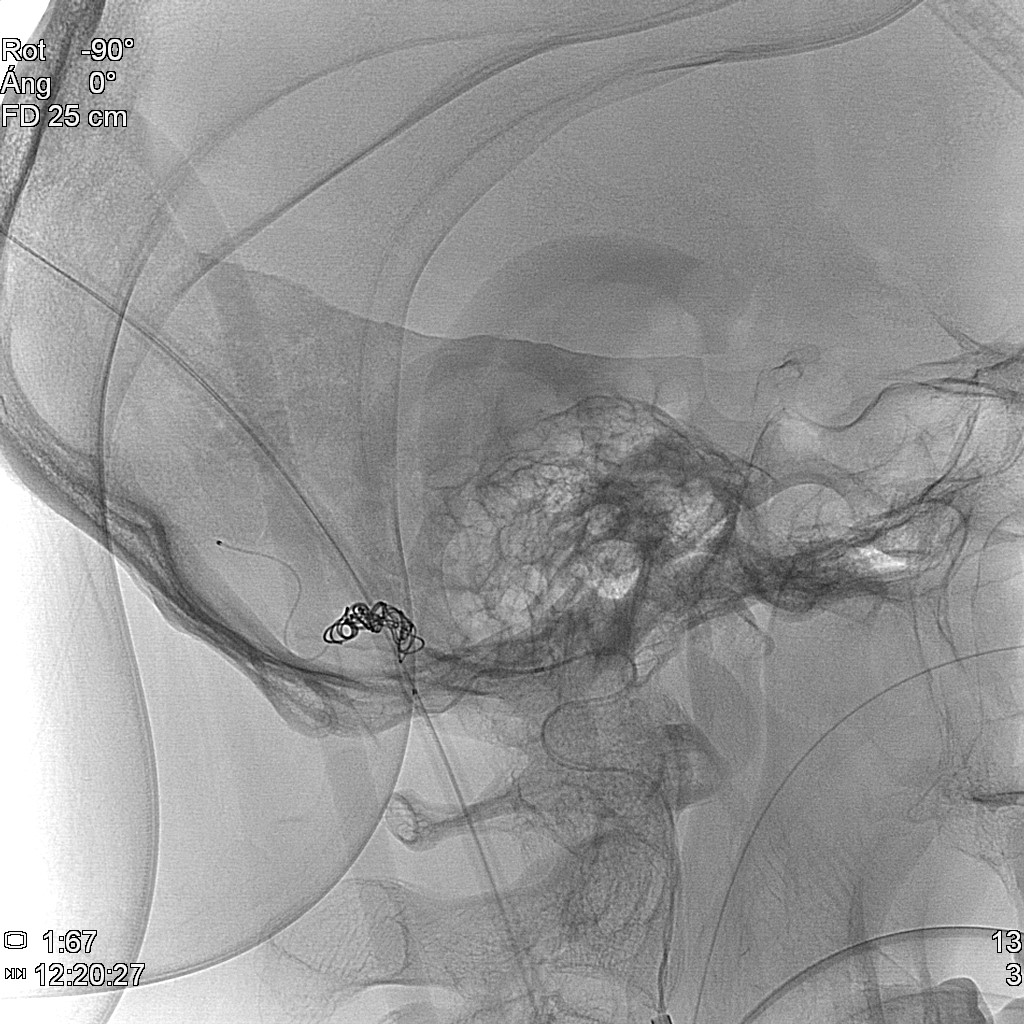

Se realiza arteriografía a las 12 horas del ingreso que muestra fístula arteriovenosa dural con aferencias arteriales de arteria occipital izquierda y drenaje a vena cortical temporal izquierda. Compatible con fístula dural Cognard tipo IV.

Podemos ver la visión lateral y AP en la figura 3:

Se decide proceder a realizar embolización de la fístula con la técnica de la olla Express para lo cual empleamos (Figura 4):